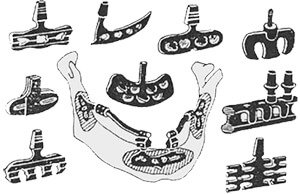

Субпериостальные (поднадкостничные) имплантаты

Устанавливаются через боковую сторону десны под надкостницу, которая располагается между десной и челюстной костью. Являются сложной системой: основой выступает разветвленная металлическая сетка анатомической формы, а вершиной — база для искусственных зубов. Тонкая и гибкая конструкция позволяет охватить большую часть тканей и обеспечить надежную устойчивость протеза или коронки.

Импланты этого типа рекомендованы для тонкой челюстной кости или при ее сильной резорбции (когда костная пластика недопустима), после длительного отсутствия зубов, для восстановления зубного ряда у пожилых людей. Могут сразу нагружаться протезом.

Трансоссальные имплантаты

Многоуровневый вид из пластин и штифтов. Часть штифтов вживляются в челюстную кость, остальные выходят с внутренней стороны десны или неба в ротовую полость и служат опорой для протеза. Пластины прилегают к краю челюсти, устанавливают в стационарных условиях под общим наркозом. Из-за высокой травматичности практически не применяются.